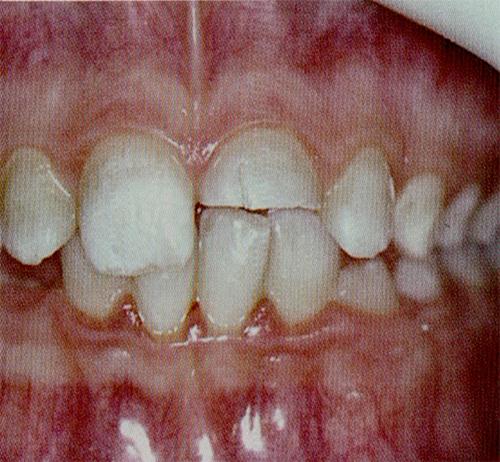

넘어져서 치아가 손상되었다면

오늘은 치아가 원치않은 충격으로 깨지거나 빠지게 되면 어떻게 해야 하는지에 대해서 알아 보려고 합니다.

치아에 손상이 가해지는 원인은 여러 가지가 있을수 있어요.

넘어졌을 수도 있고 사고가 날수도 있구요

또한 과격한 운동을 하다가도 치아에 손상이 가해질수 있어요

자 일단 치아에 충격이 가해졌다면 손상된 범위를 확인하셔야 합니다.

치아가 부분적으로 파절되고 흔들리지 않는다면 우선 안도할수 있습니다.

이런경우에는 파절된 범위에 따라 파절된 부위를 메꿔주거나 보철치료를 하면되요.

근데 치아에 충격이 많이 가해져서 치아가 흔들리거나 빠진다면 이건 매우 걱정해야 하는상황이 발생할수 있습니다. 치아를 상실할수도 있다는 것이지요.